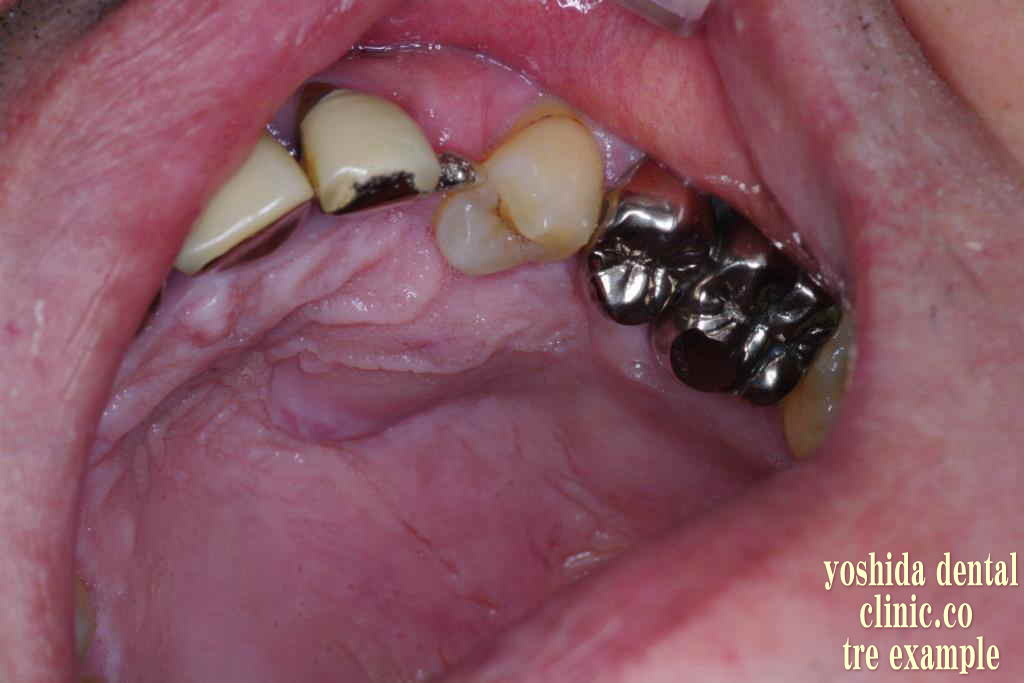

歯牙移植術(保険治療)

歯牙移植  智歯いわゆる親知らずを奥歯に移植できる場合があります。

今回、左下の臼歯が根吸収を起こしていて保存できないため、左上の智歯を下の抜歯予定部位へ移植しました。

歯牙移植レシピエントサイトの抜歯   左下の臼歯を智歯と共に抜歯して、抜歯した歯の根吸収を確認。